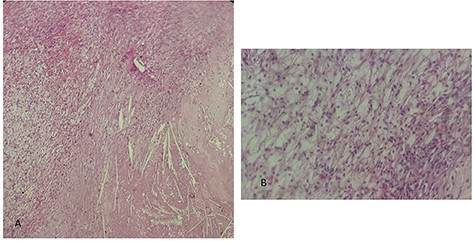

This is a 50-year-old patient with a history of medically treated renal lithiasis, who consults for left low back pain. The patient was apyretic and reported no urinary symptoms. The clinical examination was without any particularities. There was no organomegaly or lumbar contact on bimanual palpation. Biologically, there were no abnormalities, including no biological inflammatory syndrome, and renal function was preserved. The urine culture was sterile. Renal ultrasound revealed a 3-cm left cortical renal mass with moderate vascuarization. Abdominal CT scan confirmed the presence of a heterogeneous Bosniak type 3 cystic mass having a thickened wall (Fig. 1). Abdominal MRI showed a left polar cyst having an exophytic development and a thickened wall with spontaneous T2 hypointensity and T1 hyperintensity without any pathological enhancement after Gadolinium injection (Fig. 2). The retained diagnosis was an hemorrhagic benign cyst. At multidisciplinary meeting, the decision was to perform an MRI 3 months later which showed a left medio-renal cortical cystic mass measuring 24 × 28 mm having a T1 hyperintensity and heterogeneous T2 hypointensity, with a thickened wall mildly enhanced after contrast injection evoking a Bosniak type-3 hemorrhagic cyst. Seeing the MRI results, we decided to perform a left tumorectomy. Pre-operatively, the perirenal tissues were inflammatory and adherent to the capsule, a complete dissection of the kidney was performed allowing the identification of the tumor which was of a 3-cm diameter and a partially exophyctic development, then we cut the tumor with a 2-mm surgical margin. No urinary tract leakage was observed. Finally, renorraphy was performed in two plans using Vicryl 2-0 and 1 (Ethicon, Cincinnati, OH, USA). After confirming the lack of active bleeding, we placed a drainage tube and closed the incision. The total operation time was 1 h 45 min, with 18 min of selective clamping. The post-operative course was uneventful, and the patient was discharged 2 days post-operatively. The histopathological examination revealed a 2.5 × 2.7 cm necrotic lesion with an inflammatory interstitial infiltrate dissociating the epithelial structures (Fig. 3). The retained diagnosis was a pseudo tumoral Xanthogranulomatous pyelonephritis. The CT performed 3-months after surgery showed no abnormalities.

histological examination. (A) Hematoxylin Eosin × 20: inflammatory granulomatous changes in contact with cholesterol crystals. (B) Hematoxylin Eosin × 40: inflammatory infiltrate rich in xanthemous foam cells.

The histological examination usually shows a dense inflammatory infiltrate of all interstitial tissue with presence of lymphocytes, plasmocyts and neutrophils. We notice a replacement of renal parenchyma with CD68+ foamy histiocytes, occasional multinucleated giant cells and inflammatory cells.